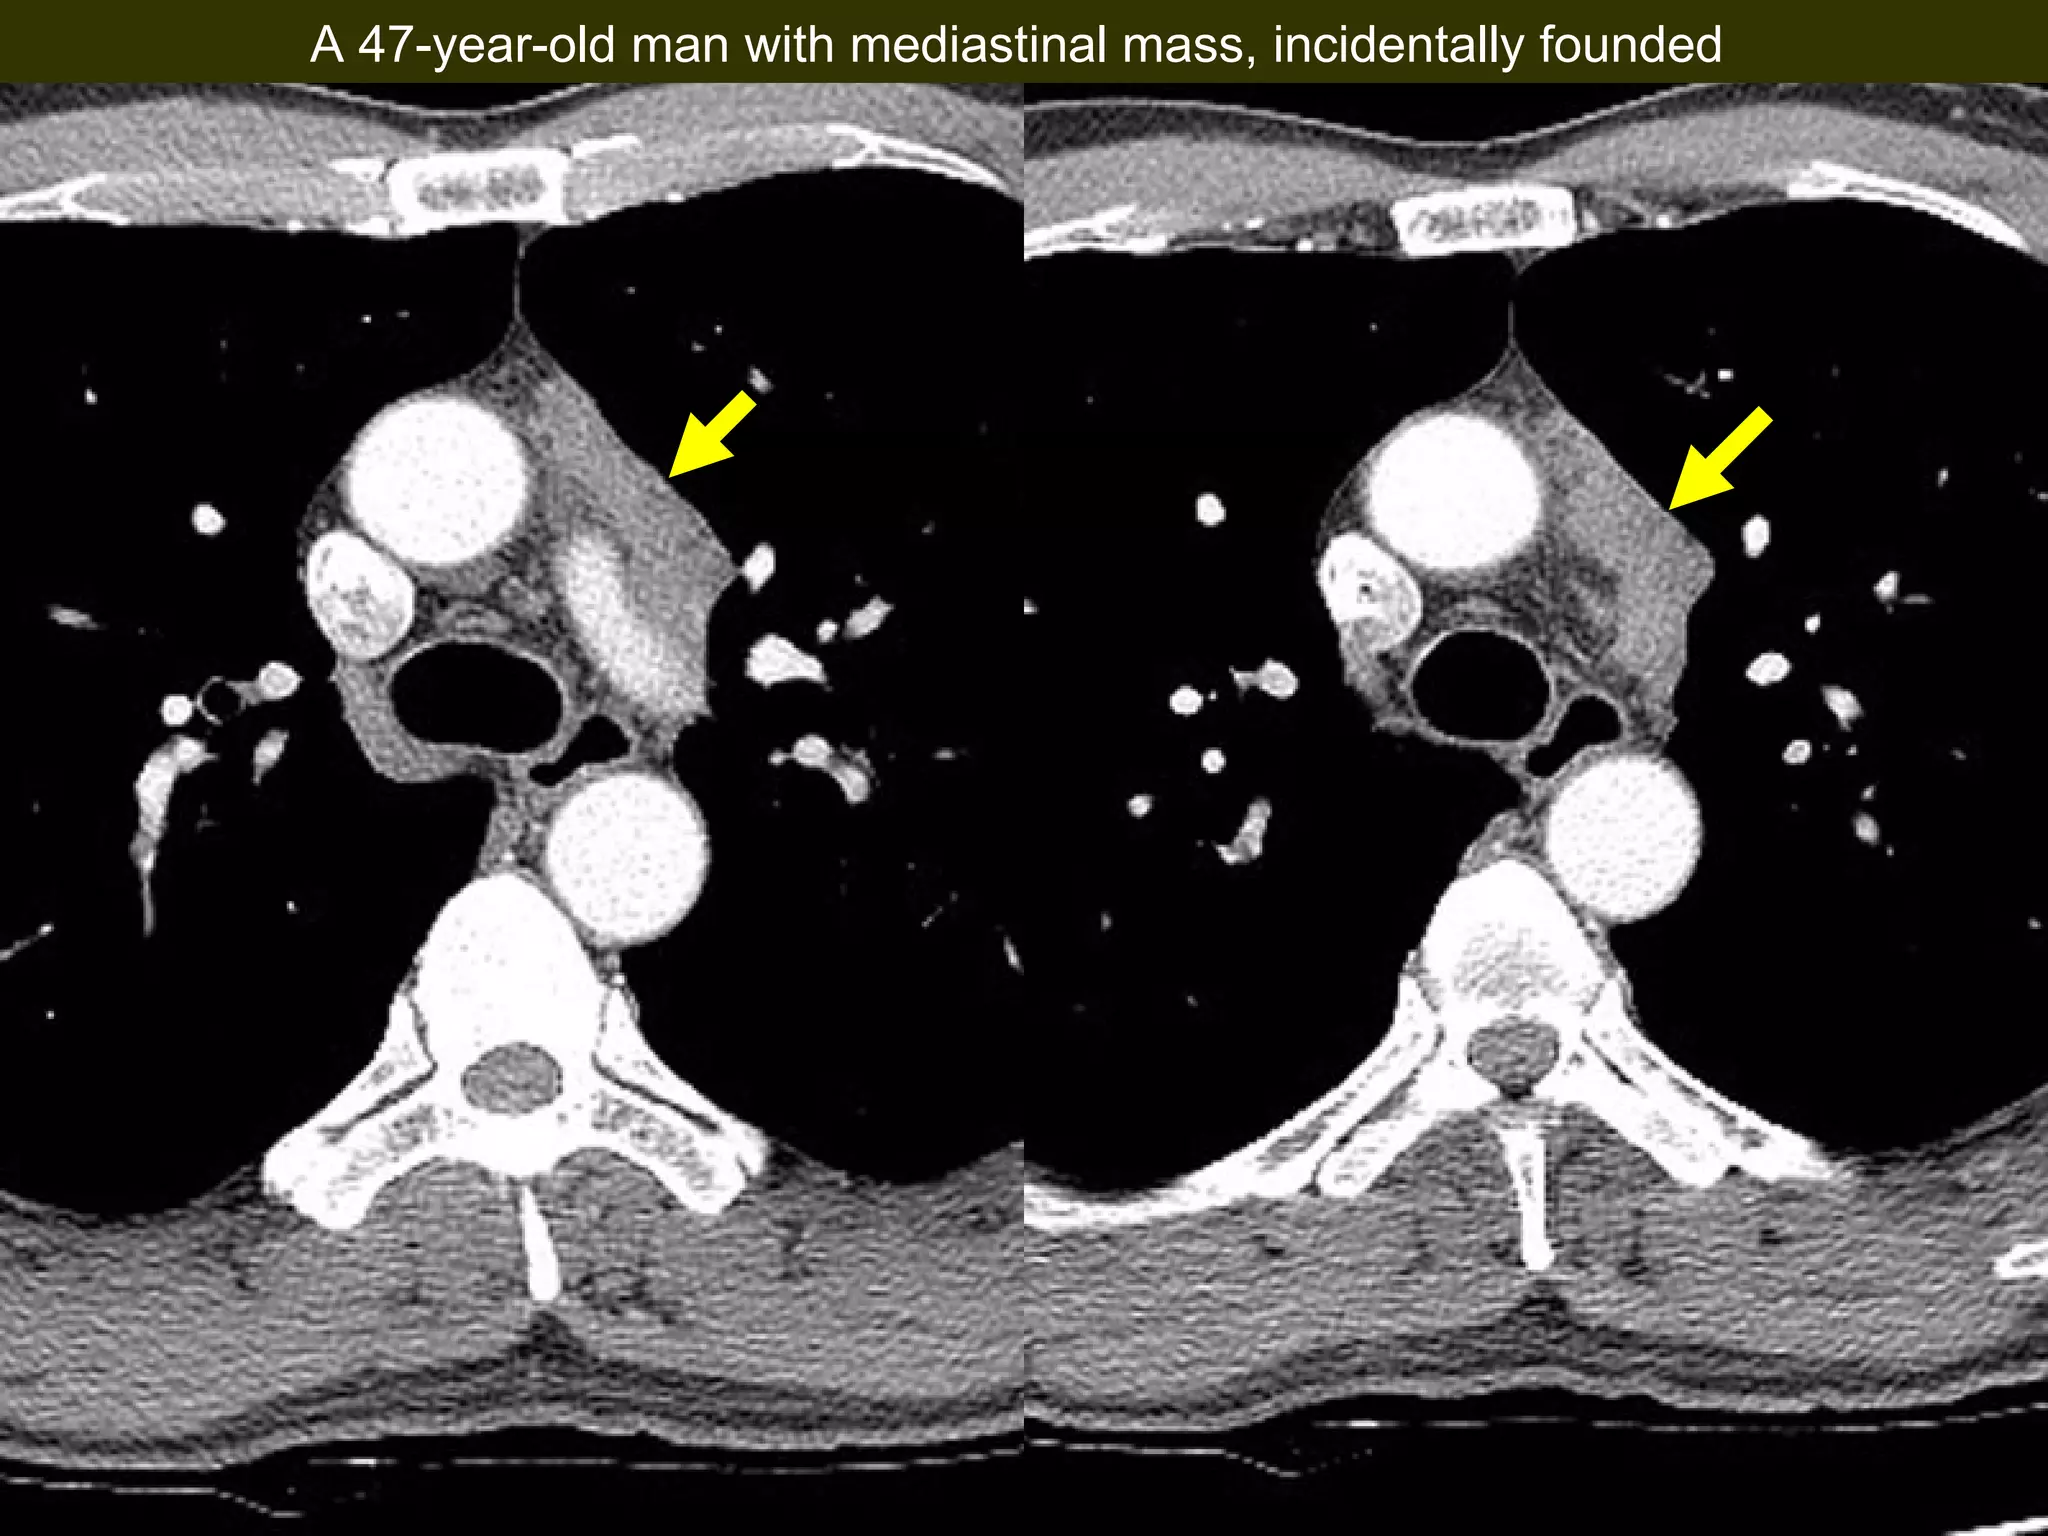

A 47-year-old man underwent a chest CT that incidentally discovered a mediastinal mass. Upon examination, doctors found that the man had a B2 thymoma, a type of thymus tumor, that contained squamous cell carcinoma. The squamous cell carcinoma had arisen within the pre-existing B2 thymoma.